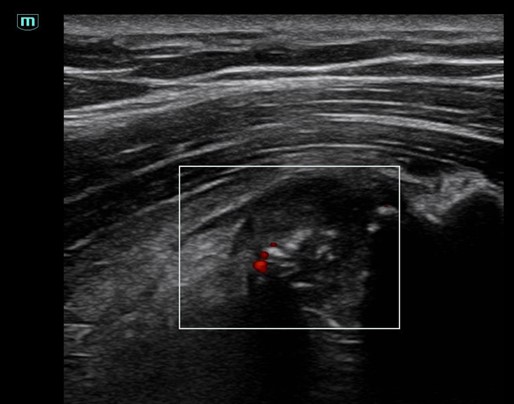

A través de varios casos clínicos se ha hecho una experiencia formativa en el C. Salud tras revisión de la literatura al respecto, se hace una sesión clínica teórica con los distintos diagnósticos diferenciales y hallazgos ecográficos y otra práctica para mostrar cómo explorar la pared torácica. Entre los casos atendidos encontramos: 3 costocondritis, una contusión pulmonar, fractura de esternón a los 15 días tras accidente tráfico, diagnóstico diferencial costocondritis vs metástasis pulmonar en paciente con cáncer de mama, varios casos de artritis de la articulación esternoclavicular, fracturas costales, seromas, hematomas, diagnóstico diferencial con linfomas, abscesos, etc.

El dolor de la pared costal supone uno de los retos más desafiantes en nuestras consultas, debido a que las causas isquémicas como las no isquémicas comparten clínica y síntomas. La ecografía clínica se posiciona como una herramienta clave para mejorar el diagnóstico diferencial del dolor torácico tanto en centro de salud como en las urgencias hospitalarias, por ser inocua, accesible y en el momento de la exploración.